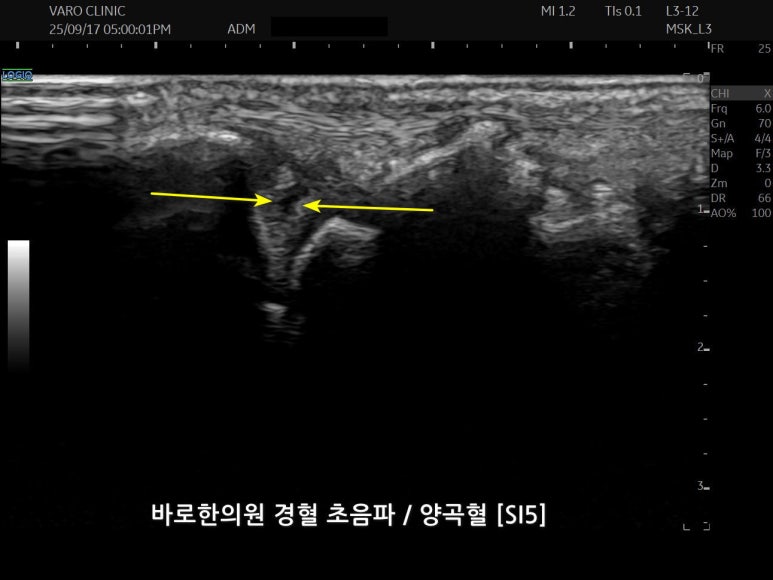

문제가 있는 혈자리를

초음파로 보면서

약침 주사를 시술합니다.

정상 조직 손상을 최소화하기 위해

가장 얇은 바늘을 사용하고,

이미 파열된 연골을 더 손상시키지 않도록

극소량으로 시작해 점차 용량을 늘려가야 합니다.

특히 완전 파열의 경우,

파열된 연골에 직접 주사하기보다

손목 관절강이나 원위 요척 관절강에 주사하여

약물이 자연스럽게 스며들도록 하는 것이

더 안전하고 효과적입니다.